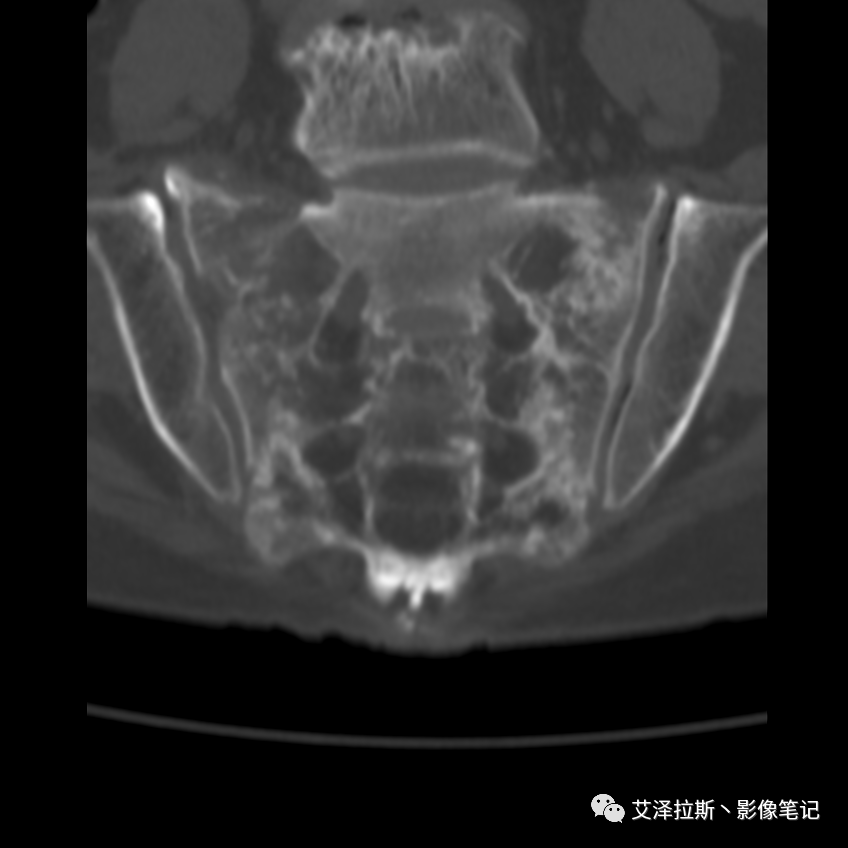

病例1:患者,女性,88岁,重度骨质疏松。

病例1

CT平扫:

影像所见

X线、CT:骶骨重度骨质疏松,双侧骶骨翼皮质断裂,分别见迂曲走行的纵行透亮线位于骶孔外侧,大致与骶髂关节间隙平行,骨折端局部可见骨痂、骨质硬化。

诊断意见

骶骨功能不全骨折